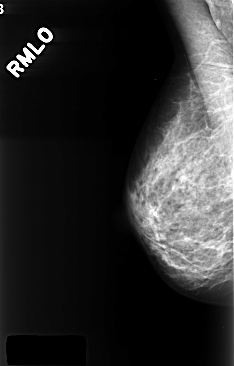

ics_version 1.0 filename C-0396-1 DATE_OF_STUDY 29 11 1996 PATIENT_AGE 68 FILM FILM_TYPE REGULAR DENSITY 3 DATE_DIGITIZED 13 10 1998 DIGITIZER LUMISYS LASER SEQUENCE LEFT_CC LINES 4376 PIXELS_PER_LINE 2864 BITS_PER_PIXEL 12 RESOLUTION 50 OVERLAY LEFT_MLO LINES 4376 PIXELS_PER_LINE 2808 BITS_PER_PIXEL 12 RESOLUTION 50 OVERLAY RIGHT_CC LINES 4392 PIXELS_PER_LINE 2760 BITS_PER_PIXEL 12 RESOLUTION 50 NON_OVERLAY RIGHT_MLO LINES 4392 PIXELS_PER_LINE 2808 BITS_PER_PIXEL 12 RESOLUTION 50 NON_OVERLAY |